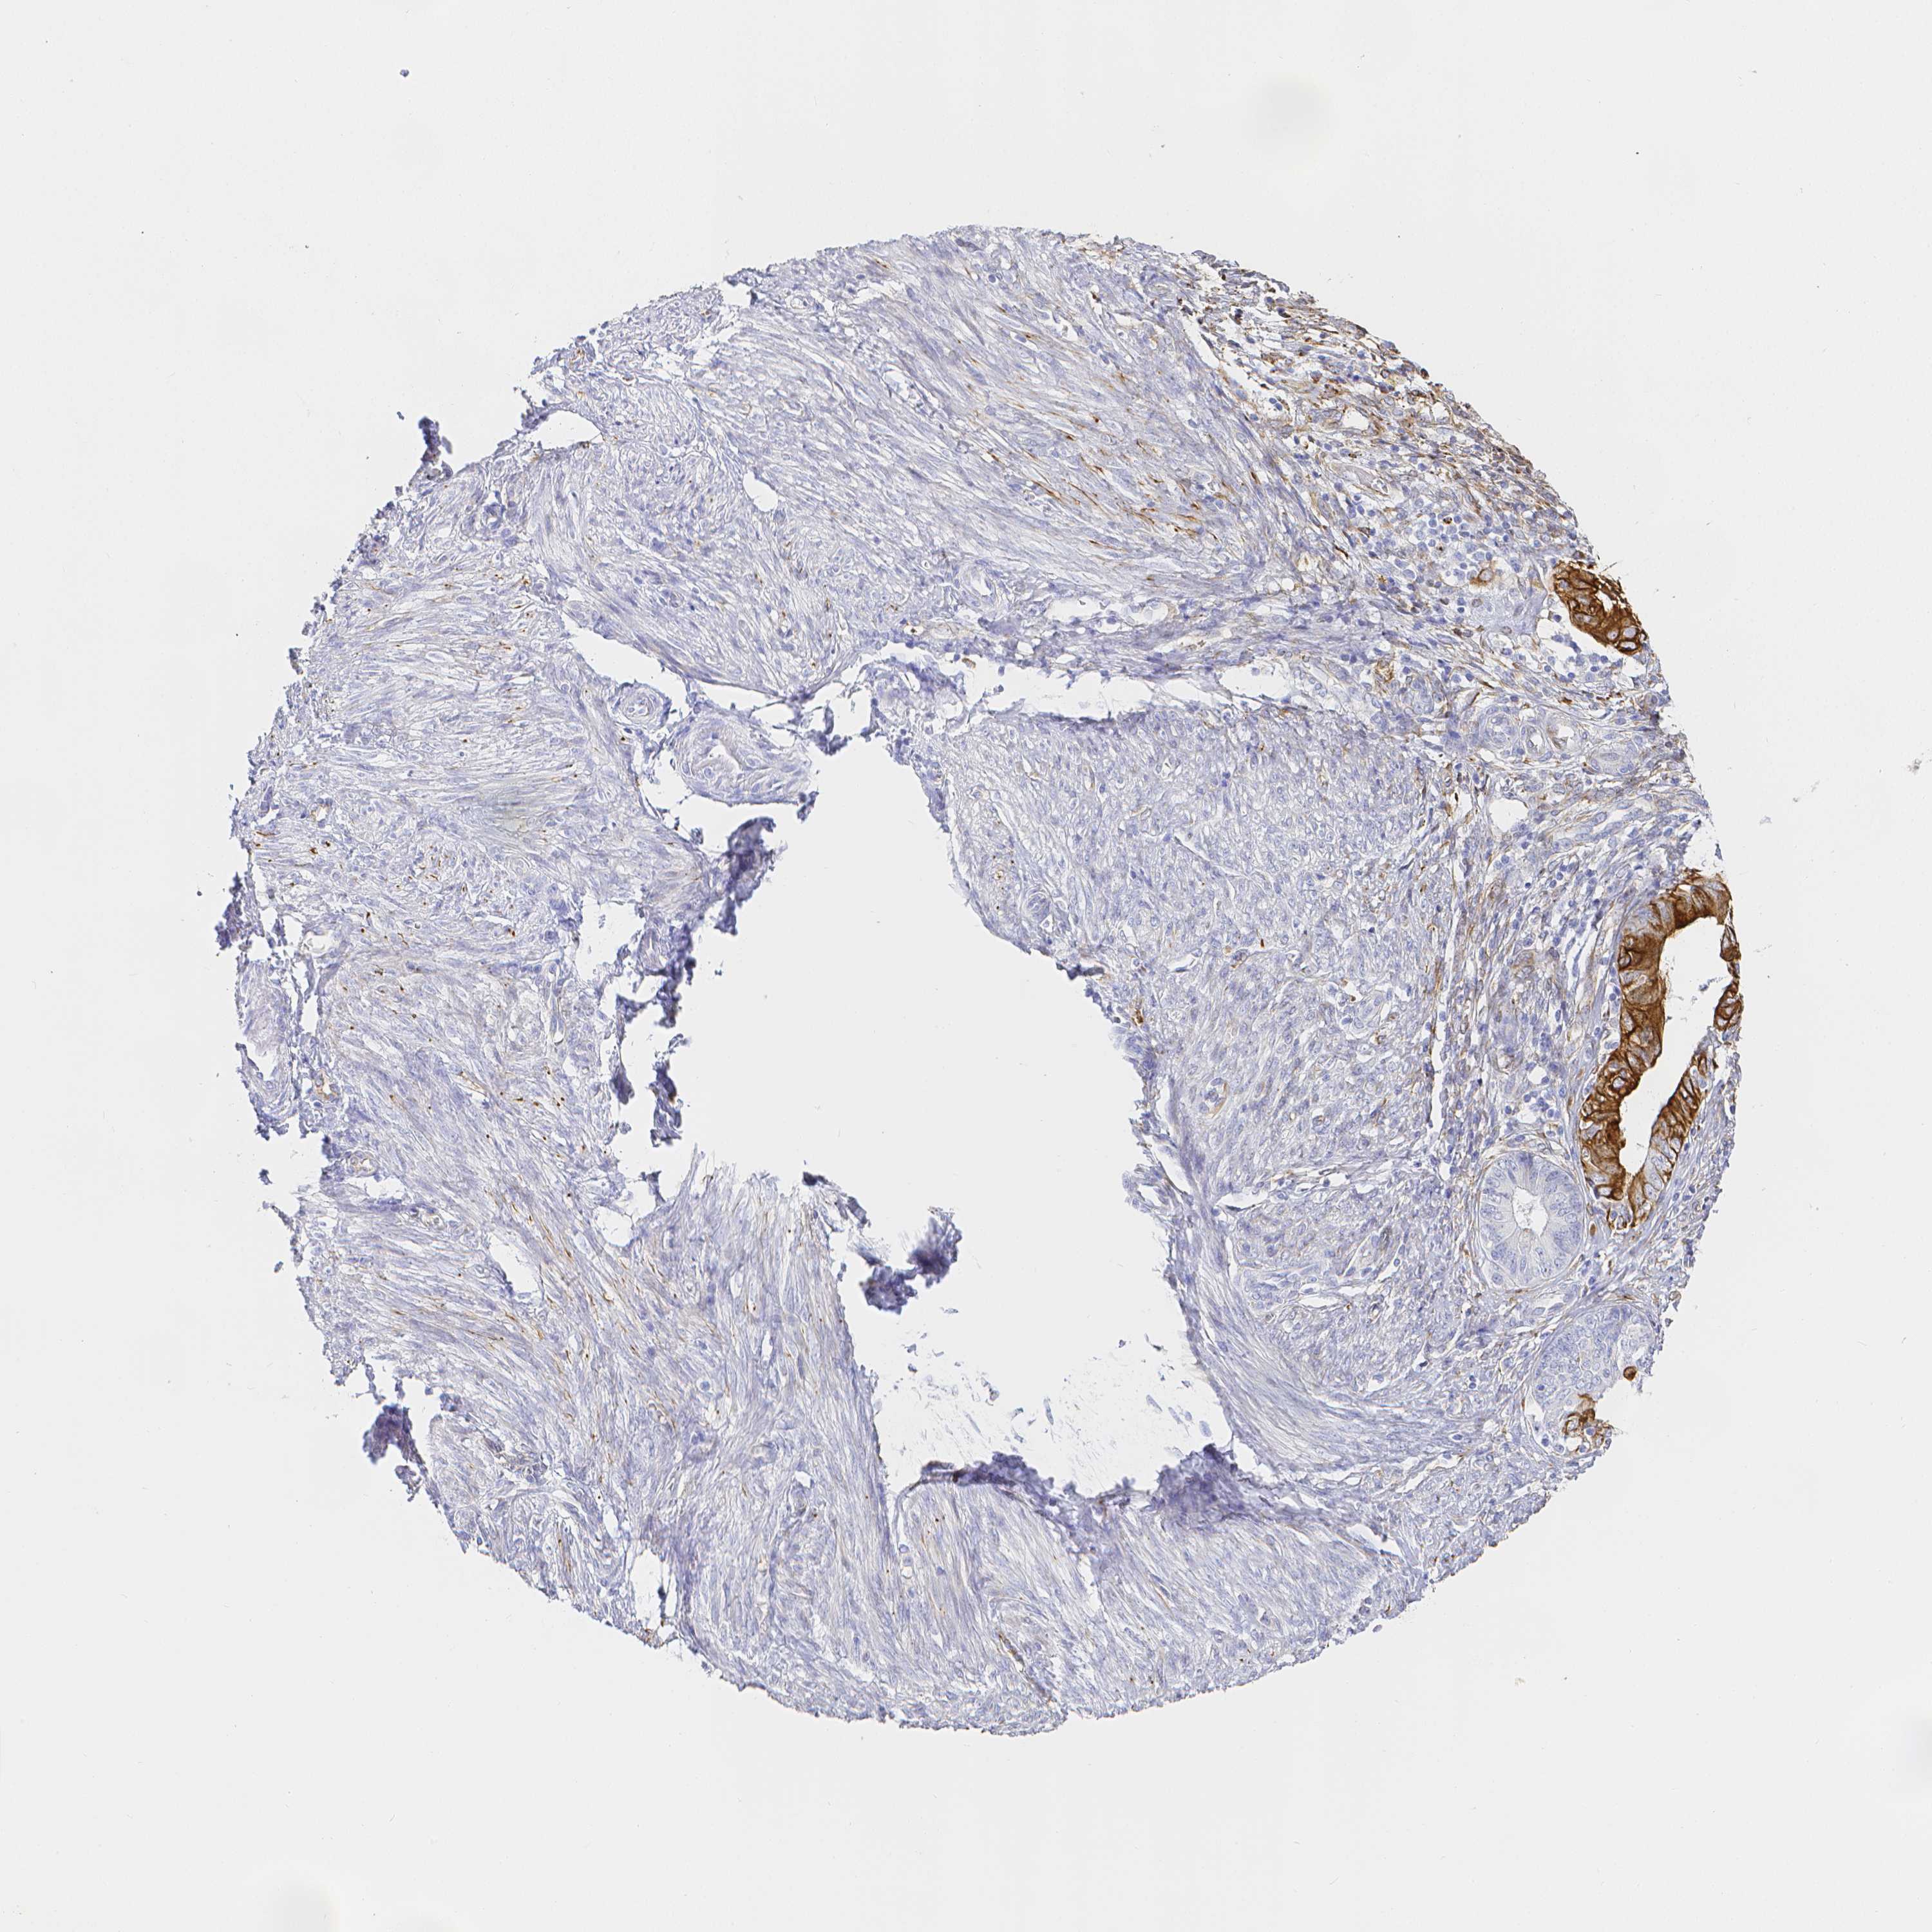

ENDOMETRIAL CANCER - Protein expressioni

A mouse-over function shows sample information and annotation data. Click on an image to view it in a full screen mode. Samples can be filtered based on level of antibody staining by selecting one or several of the following categories: high, medium, low and not detected. The assay and annotation is described here.

Note that samples used for immunohistochemistry by the Human Protein Atlas do not correspond to samples in the TCGA dataset.

Antibody stainingi

Antibody staining in the annotated cell types in the current human tissue is reported as not detected, low, medium, or high, based on conventional immunohistochemistry profiling in selected tissues. This score is based on the combination of the staining intensity and fraction of stained cells.

Each image is clickable and will lead to virtual microscopy that enables deeper exploration of all samples and also displays staining intensity scores, fraction scores and subcellular localization as well as patient and tissue information for each sample.

Antibody HPA055245

Staining

High

Medium

Low

Not detected

Intensity

Strong

Moderate

Weak

Negative

Quantity

>75%

75%-25%

<25%

None

Location

Nuclear

Cytoplasmic/membranous

Cytoplasmic/membranous,nuclear

Adenocarcinoma, NOS

Adenocarcinoma, metastatic, NOS